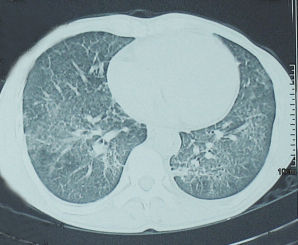

肺泡表面活性物質 胎兒胸廓受到有節律的壓縮和擴張,促使胎兒肺部產生一種叫做肺泡表面活性物質的東西,使胎兒出生後肺泡富有彈性,容易擴張。